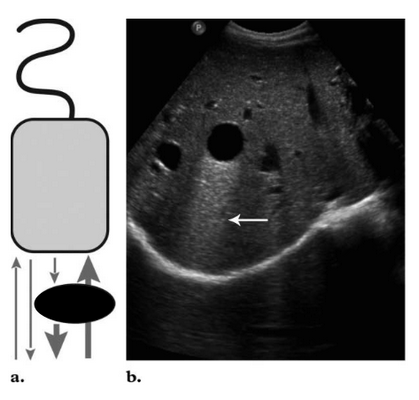

2. Эхоакустическое псевдоусиление

Этот артефакт возникает позади структур, слабо поглощающих ультразвук, т.е. позади содержащих жидкость объектов (мочевой пузырь, желчный пузырь, кисты и пр.). В некотором смысле он противоположен артефакту теней (1;4;5).

Знание этого феномена помогает в подтверждении жидкостной природы сканируемого объекта. Классическим примером является нормальное эхоакустическое псевдоусиление, появляющееся в паренхиме печени позади желчного пузыря. Эхоакустическое псевдоусиление имеет решающее значение при дифференциальной диагностике кист от новообразований с низкой эхогенностью.

Рис. 18. Артефакт периферического эхоакустического усиления . Звуковая волна слева практически не ослабляется, проходя через наполненный жидкостью пузырь, поэтому область позади него остаётся яркой. Звуковая волна справа, проходящая через паренхиму, ослабляется и затухает.

Рис. 19. Артефакт периферического усиления, возникший позади желчного пузыря.